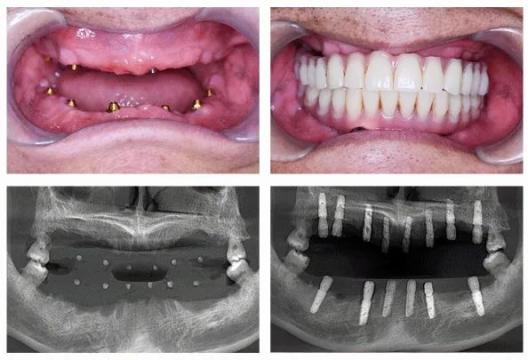

种植牙是理想的缺牙修复方式,被誉为“人类的第三副牙齿”,其优点有目共睹,相比活动假牙不舒服、难清洗、容易引起口腔黏膜病变,种植牙更稳固耐用,舒适美观,咀嚼功能好,一次种植,终生受用。

“立得用”数字化种植牙借助数字化设备,将种植体成功植入牙槽骨后,无需经过漫长的恢复期,植入当天即可在种植体上安装种植基台以及牙冠,以形成一个完整的修复体。这意味着,不管是单颗牙缺失、还是多颗、半/全口缺牙患者均可通过数字化即刻种植技术实现当天种牙,当天咀嚼美食。

专业的设备,北京种牙团队,硬核种牙技术......所有手术顾虑在这一瞬间烟消云散。无论是老年人,还是年轻人缺牙,都可以通过种植牙进行修复治疗,重获自信笑容。